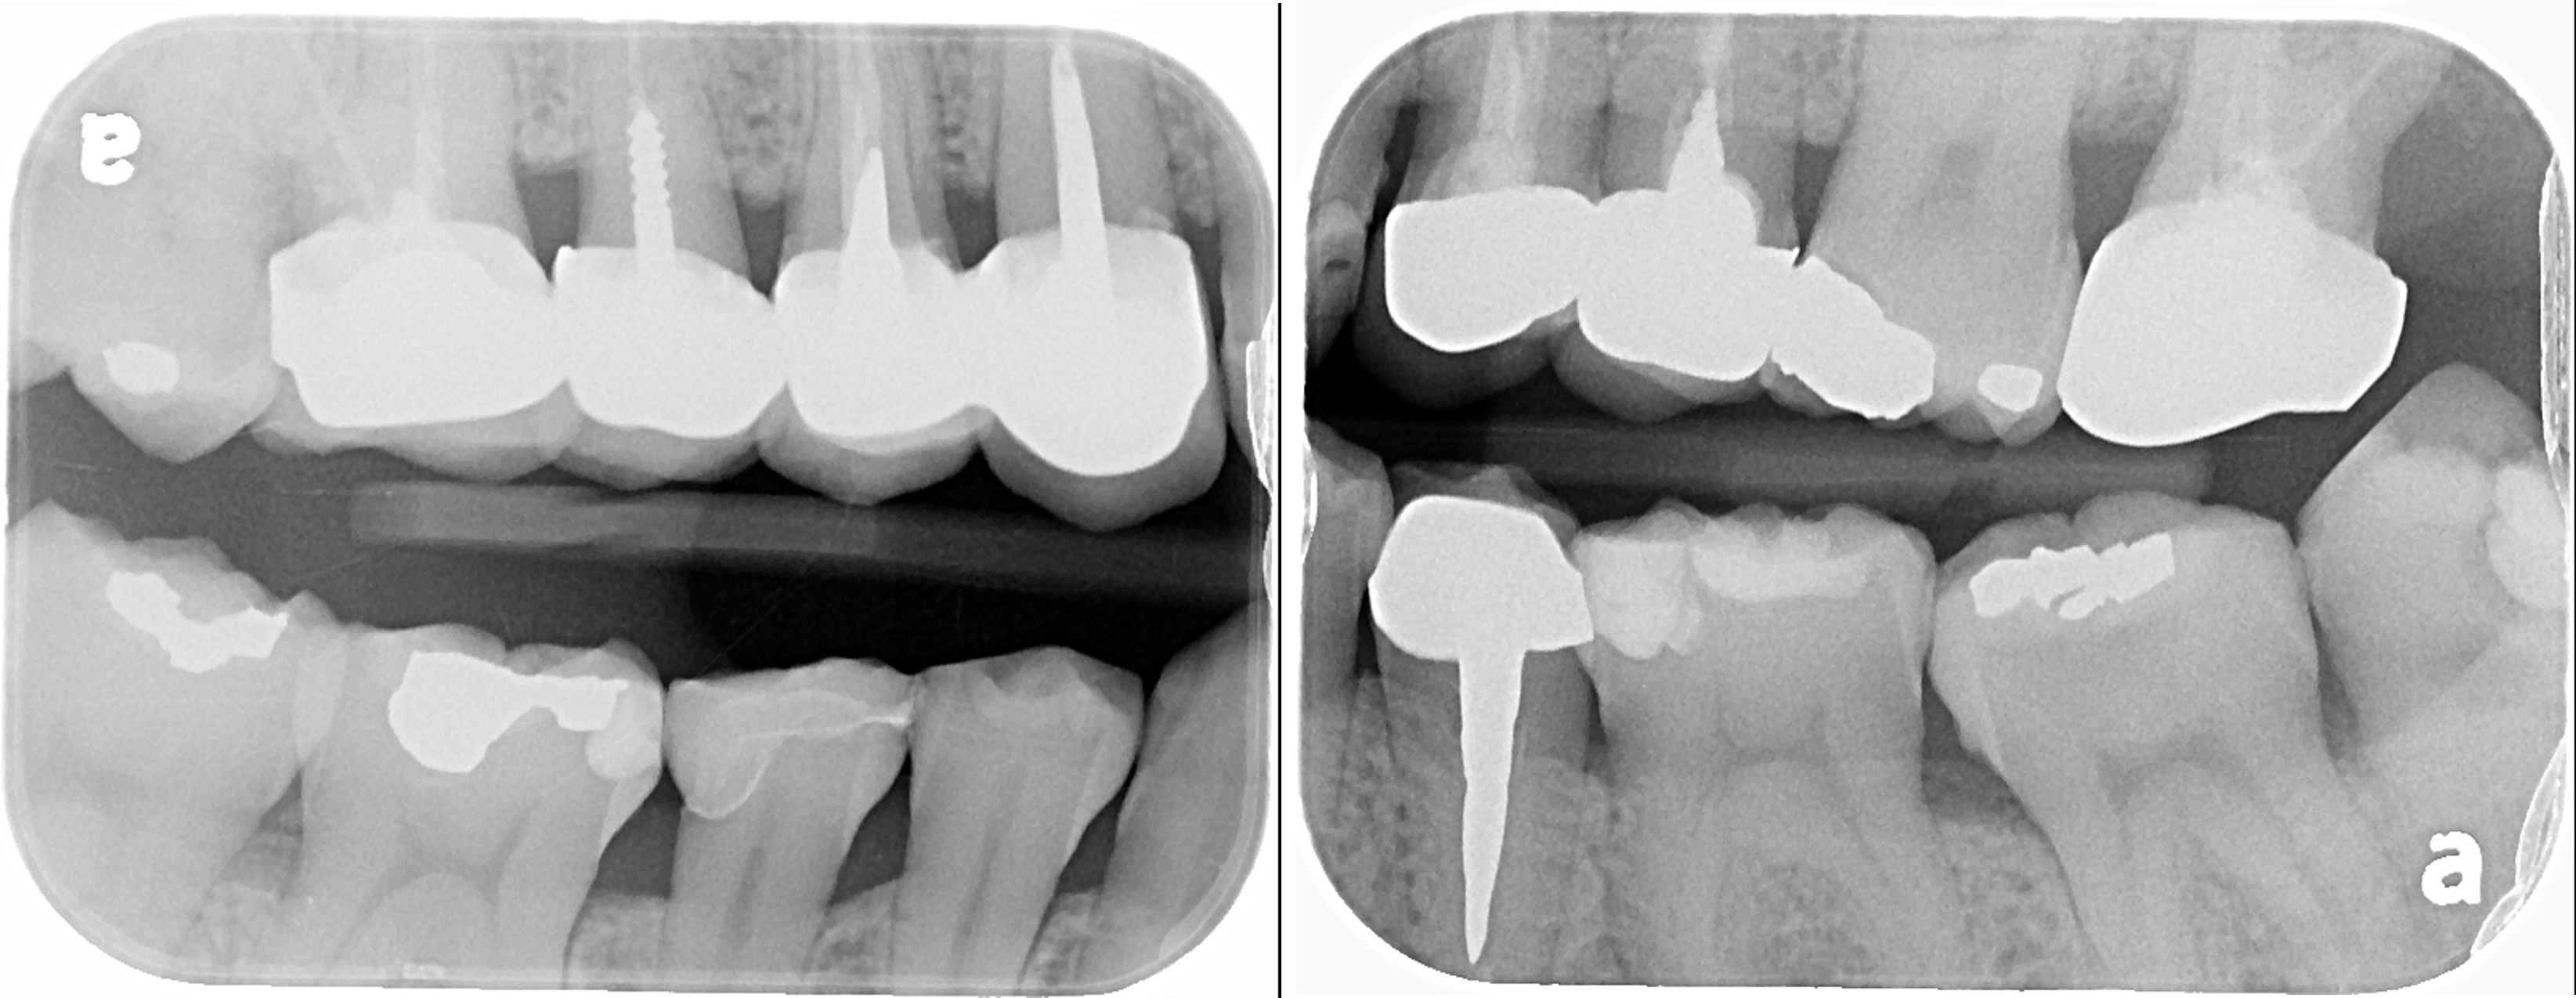

X光可見大臼齒內有蛀洞